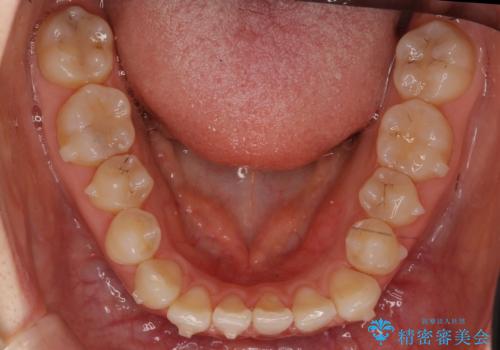

- 前歯の並びを主訴に来院。

マウスピースで歯を抜かずに治療しています。

左上の前歯が飛び出しており、唇が笑った時に引っかかっていたのが解消しています。

左上の前歯は小さいため、(矮小歯)左右対称になるようにセラミックで形を修正する治療も併用しています。

歯を大きくかぶせるスペースを作るため、右上の奥歯を後ろに下げています。

左にずれていた上の正中も揃い、大変喜んでいただきました。